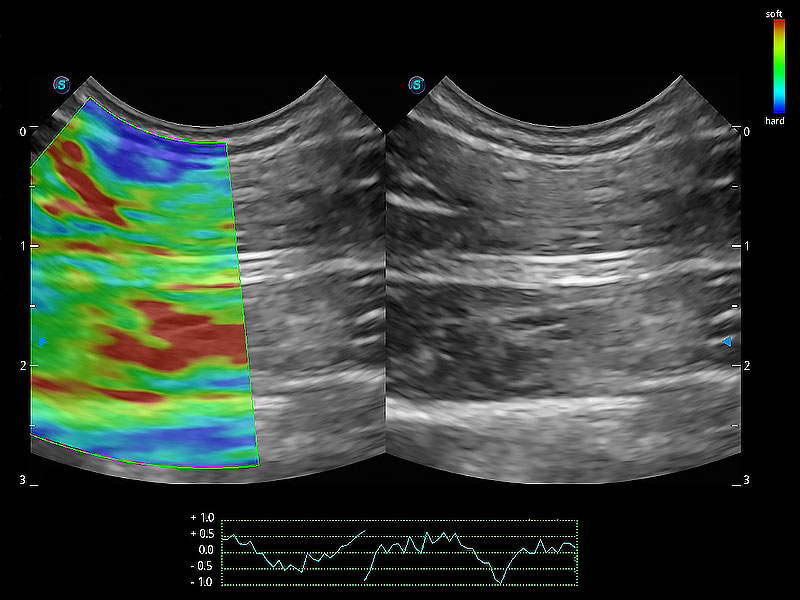

• 应变式弹性成像

操作简便,无需高频度外力作用即可真实反映组织的形变,快速评估肿瘤良恶性。

(犬)肠道